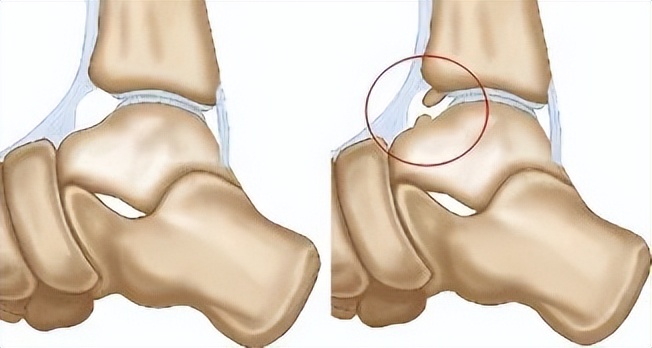

踝关节撞击综合征是指各种软组织或骨性摩擦、撞击或挤压造成的踝关节疼痛或活动受限的一组疾病,多数伴有或并发踝关节的炎性改变。损伤原因多为运动损伤,会引起踝关节周围骨赘增生、韧带损伤、松弛、软骨损伤等病理性改变。

简单点说, 踝关节撞击征就是有东西卡在了踝关节里,被骨头撞击时产生了疼痛。

踝关节前方骨赘增生,在踝关节背伸时发生撞击